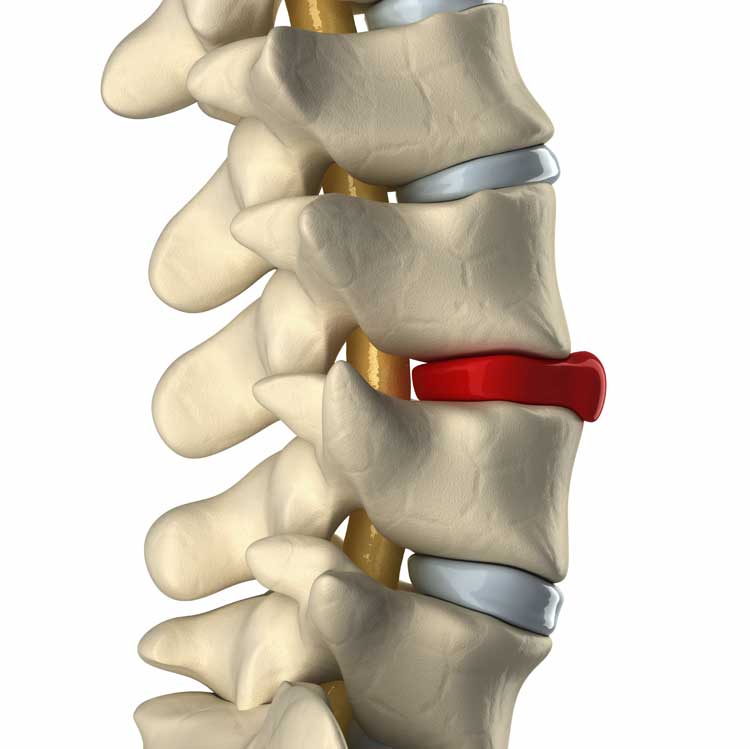

Lower Back Pain with Sciatica – Is that disc bulge really the culprit?

Disc Bulge/Herniation | Portland Physical Therapy

Herniated Bulging Disc

Bulging Discs | Nevada Pain – Las Vegas, Summerlin, Henderson